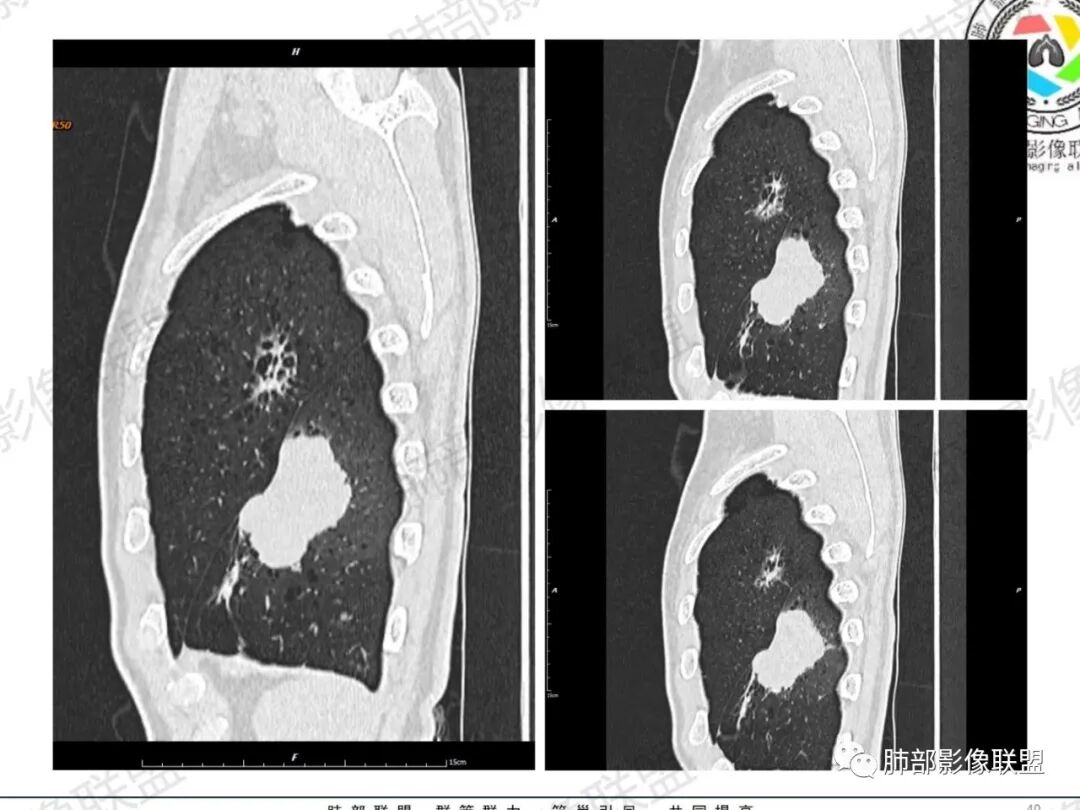

一切∮随缘:左肺下叶不规则肿块,边缘光滑,平直,局部彭隆,分叶,近端支气管堵塞,远端与胸膜相贴,平扫密度尚均匀,增强后不均匀强化,内部可见低密度坏死,胸膜下多发肺气肿,伴双肺散在光滑小结节,实验室肿瘤标志物高,考虑恶性:神经内分泌癌(大细胞),腺癌,鳞癌。

琦遇:恶性没有问题,肺气肿底子、病灶分叶、少许毛刺、叶间胸膜凹陷、部分边缘可见清晰的GGO、胸膜牵拉凹陷、局部胸水、近端支气管截断、部分支气管被推移、占位效应明显、强化特点为不均匀强化、内部有少许沼泽样低强化区,强化部分轻中强化为主、余肺可见转移性结节、左肺上叶似为囊腔型腺癌一枚,肿瘤标志物提示非小、神经内分泌,综合分析考虑大神泌、腺癌、腺鳞癌、鳞癌  同时左肺上叶囊腔型腺癌  肺转移

飞鹰行动:中年人,男性,胸疼入院,左肺下叶占位,张力较高,边界可见分叶,局部可见明显收缩性改变,增强病灶内部有延迟强化表现,考虑恶性病变,大细胞癌伴肺内转移或者囊腔样腺癌伴转移。

傅昌瑜:中老年男性,肺气肿背景,右胸背疼痛1周。CEA、NSE、CYFRA—211升高。左上肺混合磨玻璃结节,内见较多空泡和扩张支气管。左下肺胸膜下肿块,边缘较光滑,深分叶,似有血管进入,与支气管关系不清,内见不均匀强化,见沼泽地样坏死,有胸膜栽赃。另两肺多发圆形小结节。考虑恶性并肺内转移,多原发可能性大,左上肺腺癌,左下肺病理难以判断,小细胞癌?鳞癌?

LCNEC最常见的影像特征包括:(1)肿块发生部位:周围型肺癌为主,少数发生于肺中央。(2)肿块大小及形态。因肿瘤细胞生长迅速常形成较大肿块,因此其体积一般较大,直径常在3~10cm范围内,病灶常为不规则形软组织肿块。(3)肿块边界。多数学者报道大多数肿块边界清晰,边缘呈分叶状,毛刺征及“胸膜凹陷征”少见,认为与该病对周围组织浸润较轻及较少产生纤维瘢痕组织牵拉有关联。(4)肿块密度、强化特点及代谢情况。据文献报道,该类肿瘤因体积较大CT上常见软组织肿块,且多数密度不均匀,内见囊变坏死区,增强后呈轻或中度不均匀强化(可见强化者占75.7%),认为其强化特点与其内部肉眼可见坏死灶和肿瘤较大直径有关。(5)伴随症状及远处转移。该病恶性程度高,侵袭性强,常侵犯邻近结构,如胸膜、心包、邻近骨质或纵隔内组织等,易出现纵隔淋巴结转移,部分发生肺内及远处转移,少数早期可出现广泛远处转移。

LCNEC患者空洞、钙化、阻塞性肺炎、肺不张、积液这些CT特征较少见,少见支气管充气征。